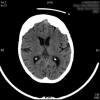

AVC amplio de territorio de A. cerebral media